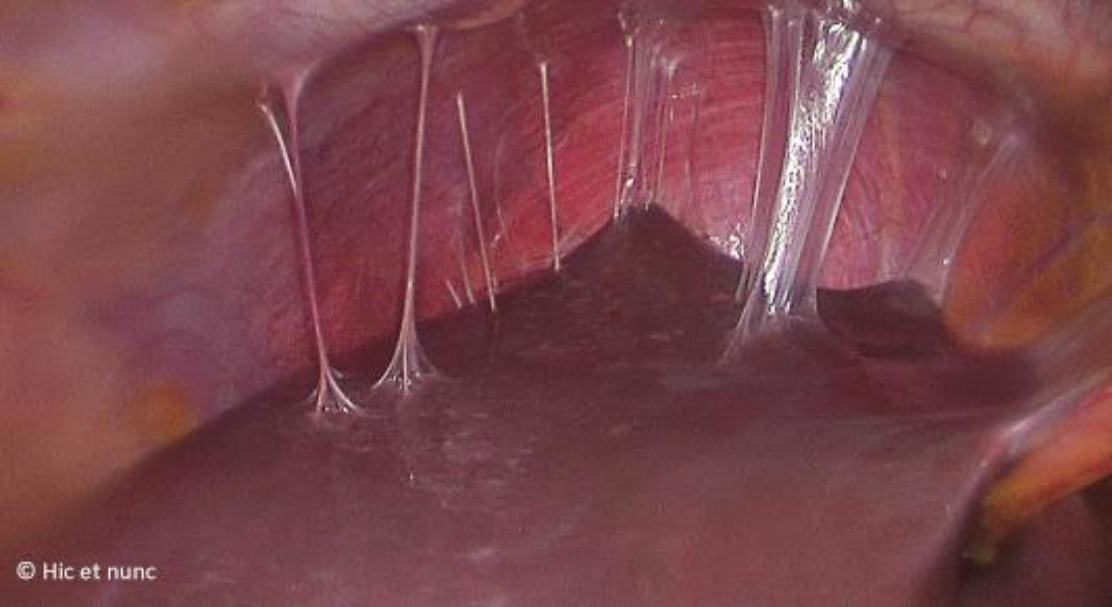

Vous décidez de réaliser en urgence une cœlioscopie exploratrice qui objective un saignement modéré au niveau du kyste de l’ovaire que vous parvenez difficilement à arrêter. En explorant la cavité abdominale vous objectivez ceci (fig. 7) :

Figure 7

Question 7 - Quelles sont les réponses vraies (une ou plusieurs réponses exactes) ?

Les adhérences « en cordes de violon » entre le foie et le péritoine sont typiques d’une périhépatite secondaire à une infection active ou à un antécédent d’infection à Chlamydia. Il s’agit d’un syndrome de Fitz-Hugh-Curtis.